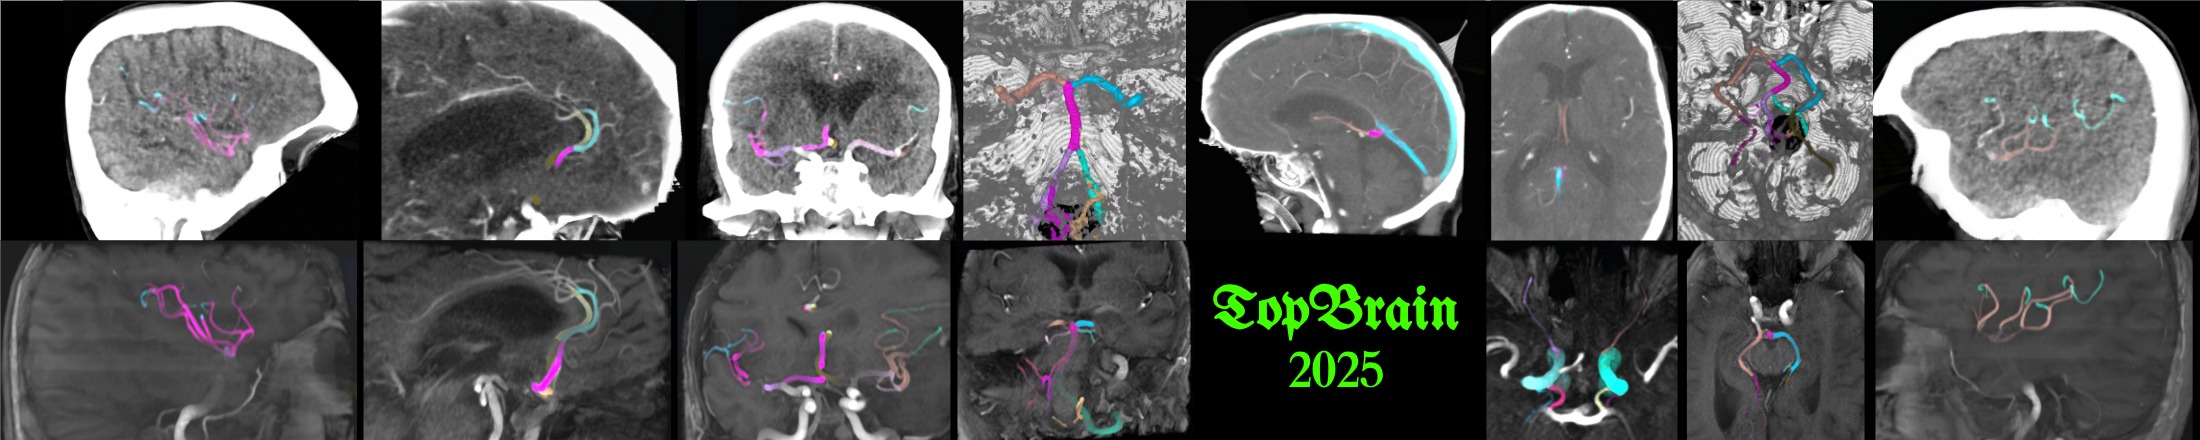

TopBrain 🔝🧠 Segmentation Challenge for Whole Brain Vessel Anatomy¶

Segment over 40 landmark brain vessel anatomies for both CTA and MRA!¶

From the team behind the TopCoW 🐮 challenge, we present a new challenge called TopBrain 🔝🧠 to segment the whole brain vessel anatomy! Previously, TopCoW focused on the the vessels from the Circle of Willis (CoW). Now TopBrain will extend upon CoW to cover all the major landmark arteries and veins of a brain angiogram!

TopBrain has 1 multiclass segmentation task for 2 modality tracks, namely CTA and MRA tracks. The input is single-modality. The task is to segment 40+ vessel classes on a CTA or MRA scan.